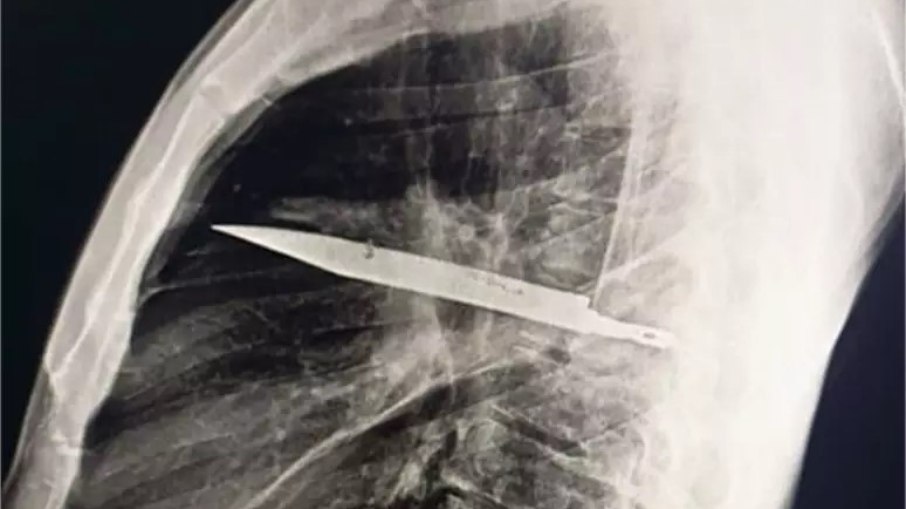

Radiografia mostra lâmina alojada no peito

Depois do relato, o paciente passou por uma radiografia, que revelou a lâmina atravessada no tórax, sem atingir órgãos vitais.